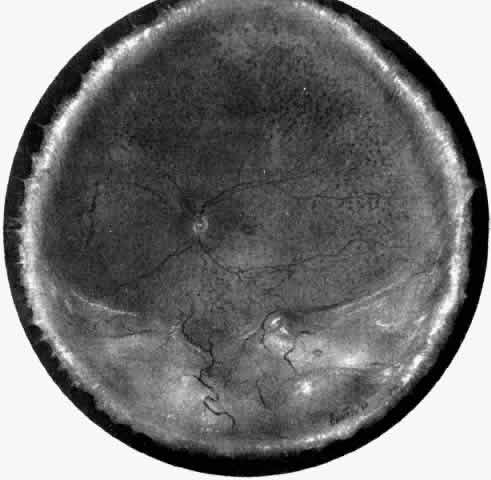

In a chronic ciliochoroidal effusion, breakdown of the blood-ocular barrier at the level of the retinal pigment epithelium (RPE) may occur, leading to a nonrhegmatogenous retinal detachment characterized by shifting subretinal fluid. The protein content of this fluid may be more than three times greater than that of plasma, causing it to shift to a dependent position as the eye and head move.21 The amount of subretinal fluid increases as the chronicity of the effusion increases. A total retinal detachment may result, making the detection of shifting fluid difficult. Linear areas of RPE hypertrophy and hyperplasia may also be observed in chronic effusions (Fig. 3). These streaks, noted by Verhoeff,22 suggest a chronic and recurrent process.

Fig. 3. Retinal pigment epithelial abnormality with streaks of hypertrophy and hyperplasia in an eye with resolving ciliochoroidal effusion. The arrowhead indicates Verhoeff's streak.22